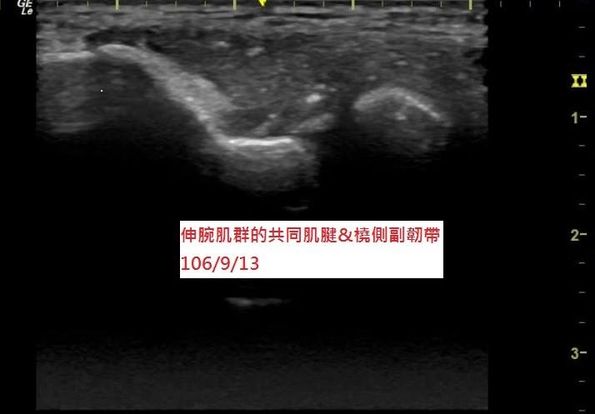

邱先生後來選擇接受『PRP注射治療』來促進肌腱修補,再搭配『體外骨震波』來治療肌腱鈣化,經過一段時間的治療後,現在邱先生手肘的疼痛幾乎痊癒,也能進行一些輕度的活動,超音波追蹤發現肌腱的破洞幾乎已經癒合,鈣化也減少許多(圖三)。